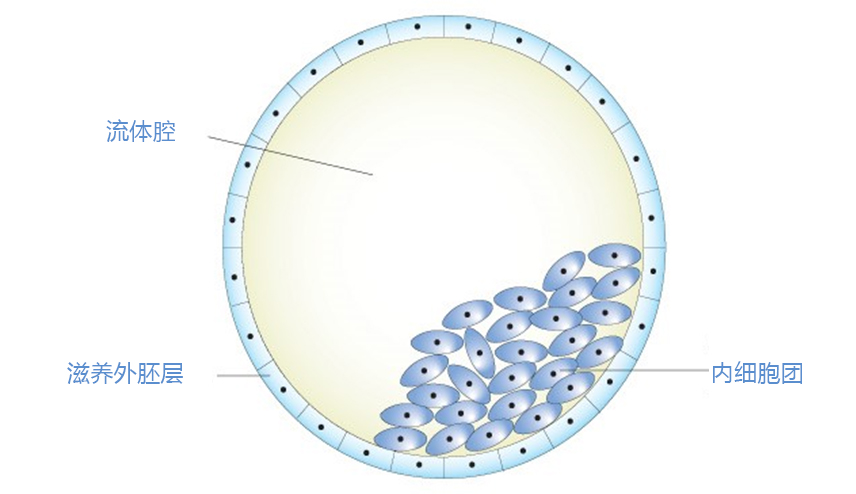

成功怀孕会经历以下几不同的阶段。- 精子必须到达并穿透并使女人的卵子受精。 - 产生的受精卵必须分裂并形成胚泡。 - 胚泡到达子宫并植入子宫内膜。 - 植入的胚泡...

试管婴儿精子和卵子结合形成受精卵,发育成胚胎,发育的胚胎需要在子宫内定居,胚胎着床需要多长时间?在卵子受精后,从输卵管到子宫需要几天的时间,胚胎继续生长和分裂,最...

囊胚培养是精子与卵子结合为受精卵后继续在培养箱内培养5至6天,然后再进行移植或冷冻的方法。囊胚培养有哪些优点呢?能够筛选掉发育潜力差的胚胎早期的胚胎(受精后第二或...